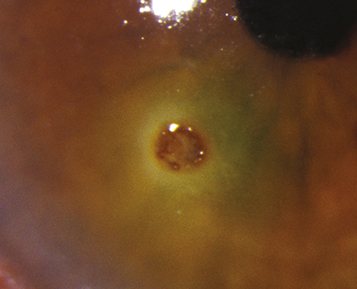

(See Figure 3.4.1.)

Figure 3.4.1: Corneal rust ring.

Conjunctival or corneal foreign body with or without a rust ring.